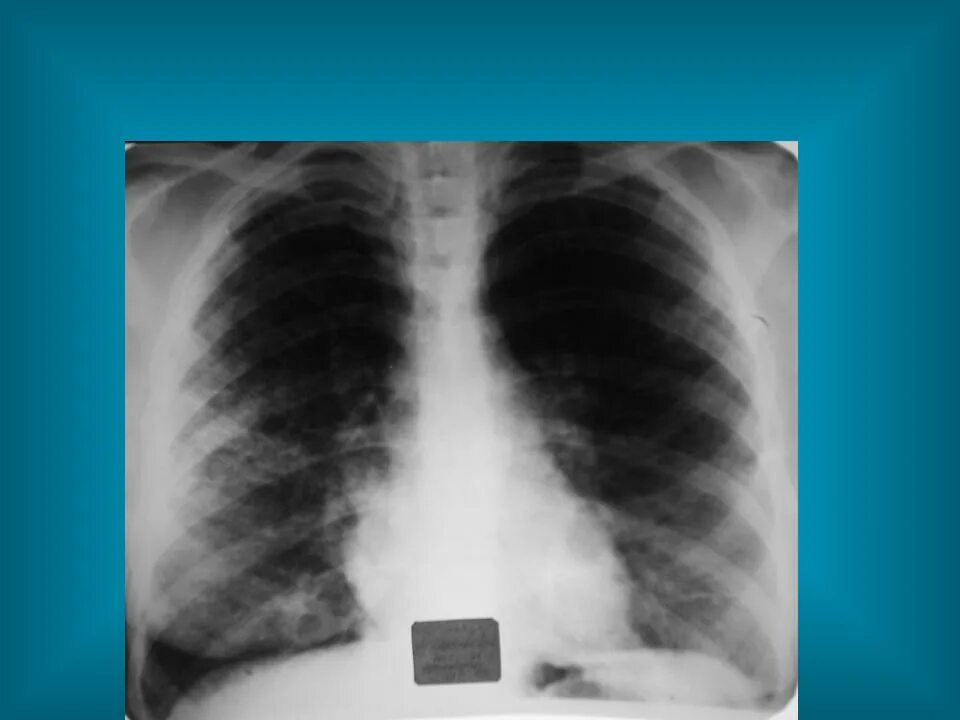

Рисунок диффузно деформирован